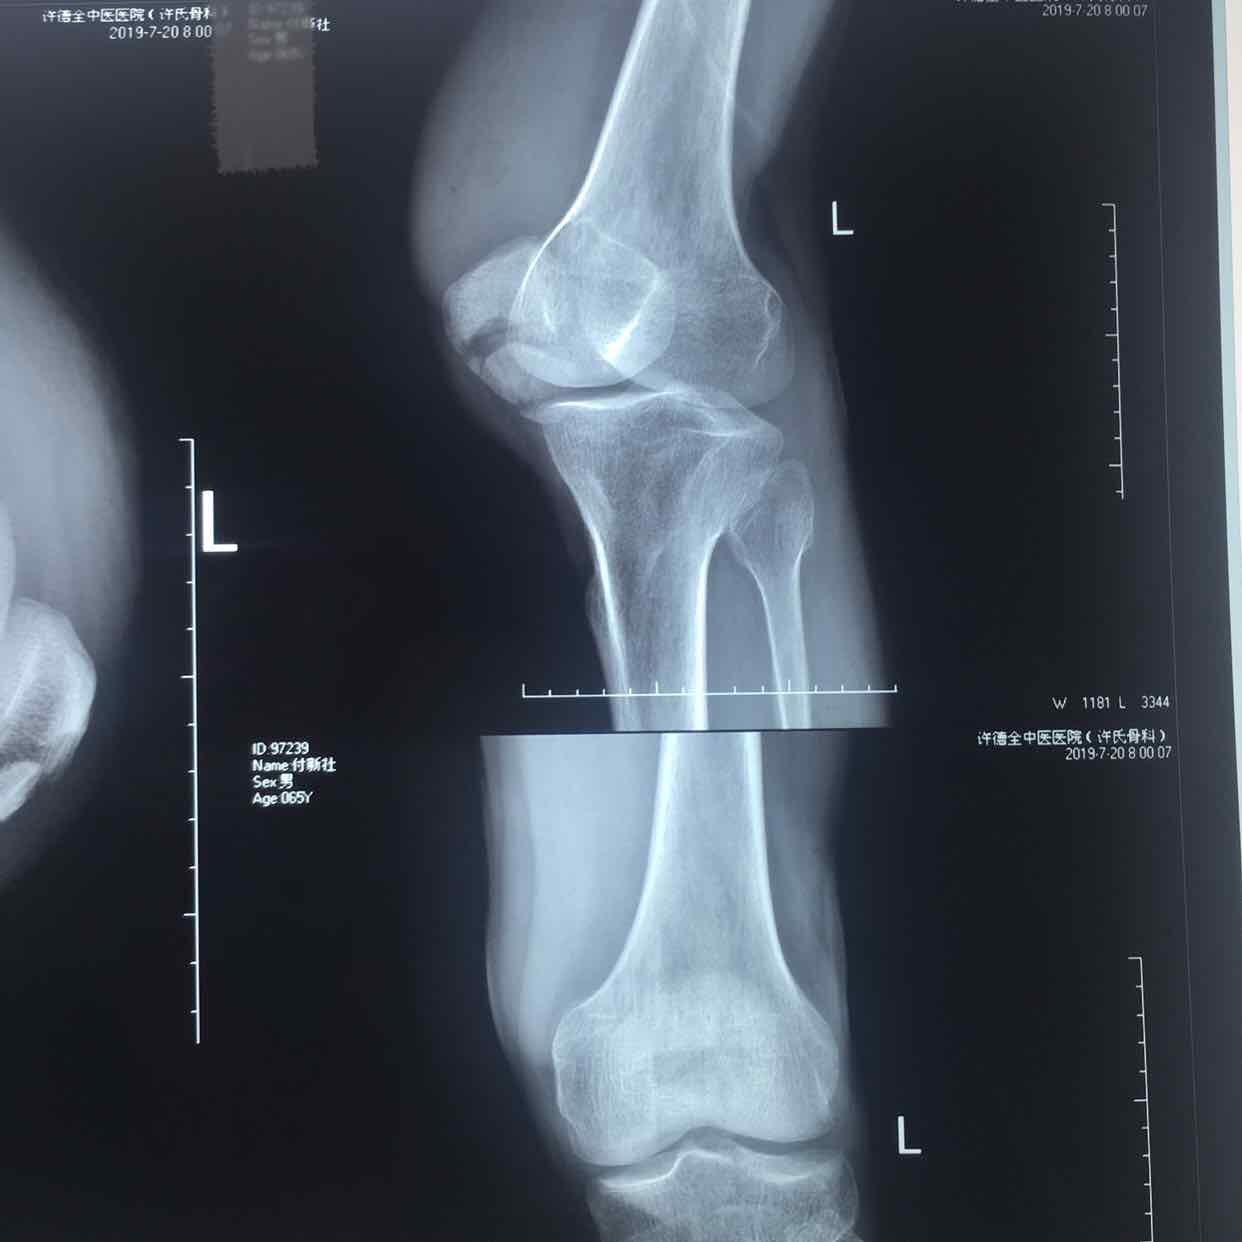

髌骨骨折(髌骨爪➕克氏针固定)

骨折 髌骨骨折

摔伤后左膝部肿痛,活动受限1小时入院。既往身体健康,无特殊不良嗜好。

生命体征平稳,心肺复未见异常。左膝部肿胀明显,局部皮色皮温正常,压痛明显,可及骨檫音,骨檫感,伸膝关节受限,末梢血运感觉正常。

诊断左髌骨骨折在腰麻下行切复内固定术,术后抗炎,消肿等处理。